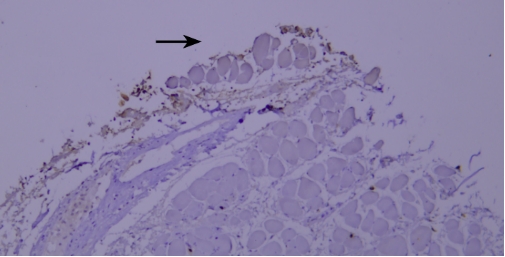

(V) Tissue Drying IssueTypical example:

TIMP-1 staining of paraffin-embedded human prostate tissue sections showed false negatives due to tissue drying (indicated by black arrows).

Recommendation for Resolution: Using a buffer supplemented with Tween-20 can effectively prevent section drying.

(VI) Edge Effect IssueTypical example:

Lysozyme staining of paraffin-embedded human tonsil tissue sections showed non-specific staining due to edge effect (indicated by black arrows).

Recommendation for Resolution: Ensure firm adhesion between tissue sections and glass slides, and completely cover the tissue with reagents to prevent section drying; using a buffer supplemented with Tween-20 can reduce the occurrence of edge effect.